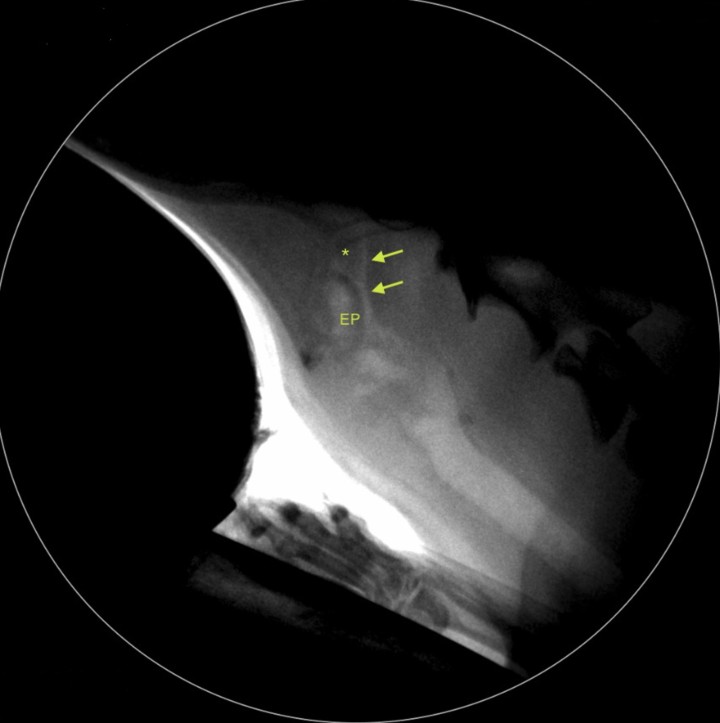

La fluoroscopia es empleada en el perro principalmente en el estudio dinámico de las vías aéreas para poder valorar la forma y el tamaño traqueal y evaluar la presencia de colapso. En este caso, la fluoroscopia mostró que el diámetro traqueal era normal, con una buena adaptación seccional a las fases de la respiración y sin evidencia de colapso. Durante el estudio, el paciente presentó una crisis respiratoria obstructiva, momento en el que se observó el desarrollo de un colapso faringolaríngeo (Fig. 3).

<p>Imagen durante la fluoroscopia en inspiración en la que se evidencia el colapso faringolaríngeo dinámico. Nótese el estrechamiento (flechas) entre el paladar blando (asterisco) y la epiglotis (EP).</p>

Imagen durante la fluoroscopia en inspiración en la que se evidencia el colapso faringolaríngeo dinámico. Nótese el estrechamiento (flechas) entre el paladar blando (asterisco) y la epiglotis (EP).

La sintomatología típica en perros con obstrucción traqueal por presencia de una neoplasia incluye disnea inspiratoria, jadeo, tos, sibilancia o colapso.[ Piirainen KJ, Viitanen SJ, Lappalainen AK, Mölsä SH. Intraluminal tracheal lipoma as a rare cause of dyspnoea in a dog. Acta Vet Scand 2018; 60: 59-64. [PubMed] ] Los signos clínicos son más evidentes cuando el tumor ocluye más del 50 % del diámetro de la tráquea.[ Mahler SP, Mootoo FA, Reece JLM, Coopery JE. Surgical resection of a primary tracheal fibrosarcoma in a dog. J Small Anim Pract 2006; 47: 537-540. [PubMed] ] En nuestro paciente, la severa reducción del diámetro traqueal provocaba un aumento exponencial de la resistencia al flujo de aire, lo cual predispuso al colapso laríngeo. Además, en su caso particular se relacionaba con un desplazamiento caudal inusual de la epiglotis que llegaba a ocluir completamente la glotis, tal como fue evidenciado durante la endoscopia. Estos episodios de alta presión negativa sobre la vía aérea alta determinaron también la aparición de colapso faríngeo, que fue detectado en la fluoroscopia. En conjunto, la vida del paciente estaba severamente comprometida siendo necesaria la resección quirúrgica de la masa.